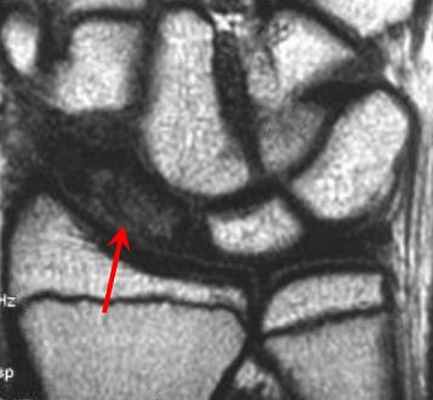

(Справа) МР-артрография в режиме Т1ВИ FS, коронарный срез: определяется консолидированный перелом дистального отдела лучевой кости. Конгруэнтность суставных поверхностей нарушена. В ладьевидно-полулунном промежутке видна рубцовая ткань. Отмечается распространение контраста в среднезапястный сустав, что, вероятно, обусловлено рубцеванием или сбросом контрастного препарата из лучезапястного сустава в дистальный лучелоктевой сустав через дефекте ТФХК. (Слева) Артрография, заднепередняя проекция, кисть отклонена в локтевую сторону: визуализируется увеличение ладьевидно-полулунного промежутка, однако контрастный препарат в среднезапястный сустав не поступает.

(Справа) МР-артрография в режиме Т1ВИ FS, коронарный срез, этот же пациент: отмечается, что ладьевидно-полулунная связка интактна. Выявленные изменения свидетельствуют о ее заживлении после разрыва.

• Контраст при артрографии через дефект в ЛПС может распространяться из лучезапястного в среднезапястный сустав и наоборот:

о Также контрастный препарат может поступать в среднезапястный сустав через дефект в ПТС

о При оценке рентгенограмм дифференцировать разрыв ЛПС от разрыва ПТС можно по характеру распространения контрастного препарата на ранних этапах процедуры